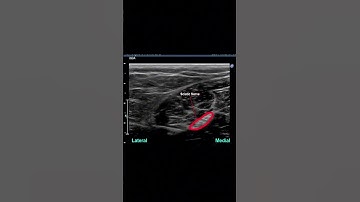

How to handle a super hard sciatic nerve block